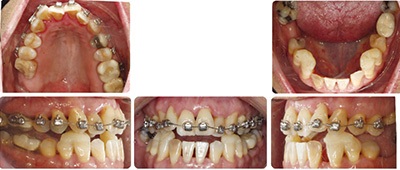

Despite significant IPR throughout treatment, these dark triangles are still obvious in her final smile. I was tempted to continue with further IPR for aesthetic reasons but here is my rationale for not doing so. In order to decrease the most aesthetically prominent dark triangles, which are in her maxillary anterior teeth, I would need to also perform more IPR in her lower anterior teeth to allow the overjet to couple appropriately. Remember that Shelley’s lower incisors were the teeth that were of greatest periodontal concern at the start of treatment. The lower incisors were also in a slightly more compensated/upright position to begin with in her forward mandible. When I closed her pre-existing mandibular anterior spaces these teeth uprighted a bit more. When I performed IPR throughout treatment on the lower anterior teeth to minimize the dark triangles and then closed those spaces, these teeth uprighted a bit more again. You can see the change in angulation of these teeth when comparing pre to posttreatment ceph images. Despite my distaste for dark triangles in the smile, I did not think it wise to further decrease the labiolingual inclination of these teeth any further with continued IPR.

Shelley’s treatment finished in 20 months and she and her general dentist were very satisfied with her outcome. The key takeaways from this unique case are: